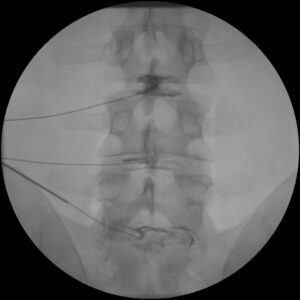

During a Discogram, a physician can identify which disc is causing you discomfort by injecting dye into one or more discs and viewing them on an x-ray or CT scan. The procedure helps doctors know which disk to treat — or sometimes surgically remove.

- Insert a needle into your back and into the center of a disc

- Inject dye into the disc and then remove the needle

After the injections, you might need to have an x-ray or CT scan of your injected discs. If the injected dye has spread from the center of a disc, that means the disc has tears and is damaged.